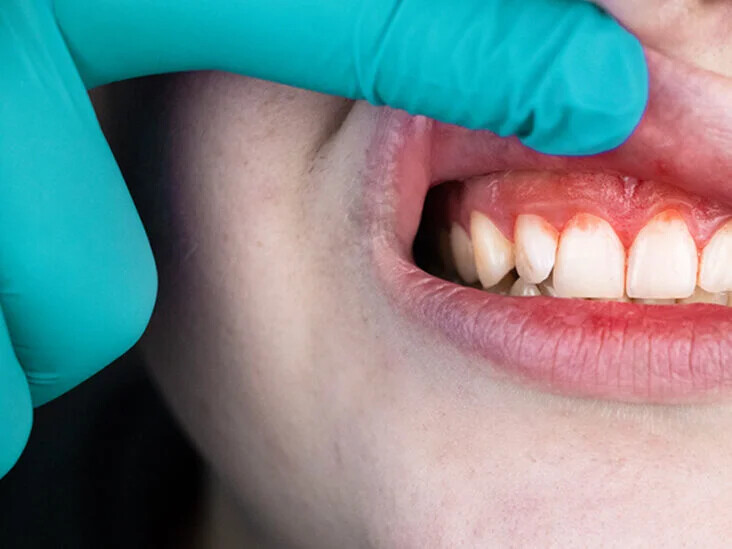

If there is swelling around just one tooth in your mouth, it may be because you didn't brush or floss correctly, leaving behind food debris that cause tooth cavities and inflammation in the neglected area. Over time, such inadequate oral hygiene can also lead to gum disease. Be on the lookout for pale, red or swollen gums, as well as bleeding while brushing, pus coming from the tooth, a loose tooth, or persistent bad breath and taste.

2. Gum Disease

A common trigger of a swollen gum around one tooth, gum disease is a prevalent condition for which you should be on guard each time you brush. In its earliest stages, the condition's symptoms show up as red and swollen gums that, although painless, might still bleed. As the disease progresses, it can cause loose teeth due to gums that have pulled away in certain spots.

How to Prevent Swollen Gums

It's not enough to just brush your teeth twice a day; flossing in between your teeth and using an effective mouthrinse are just as important. In addition, make sure you're brushing, flossing and rinsing with proper tools and the right technique. If you have a large space between two teeth, for instance, an interdental brush can help clean in between them. Of course, you should be going for your dental check-ups twice a year so your dentist can check not only the overall health of your teeth, but also whether your gums have receded or started to swell.